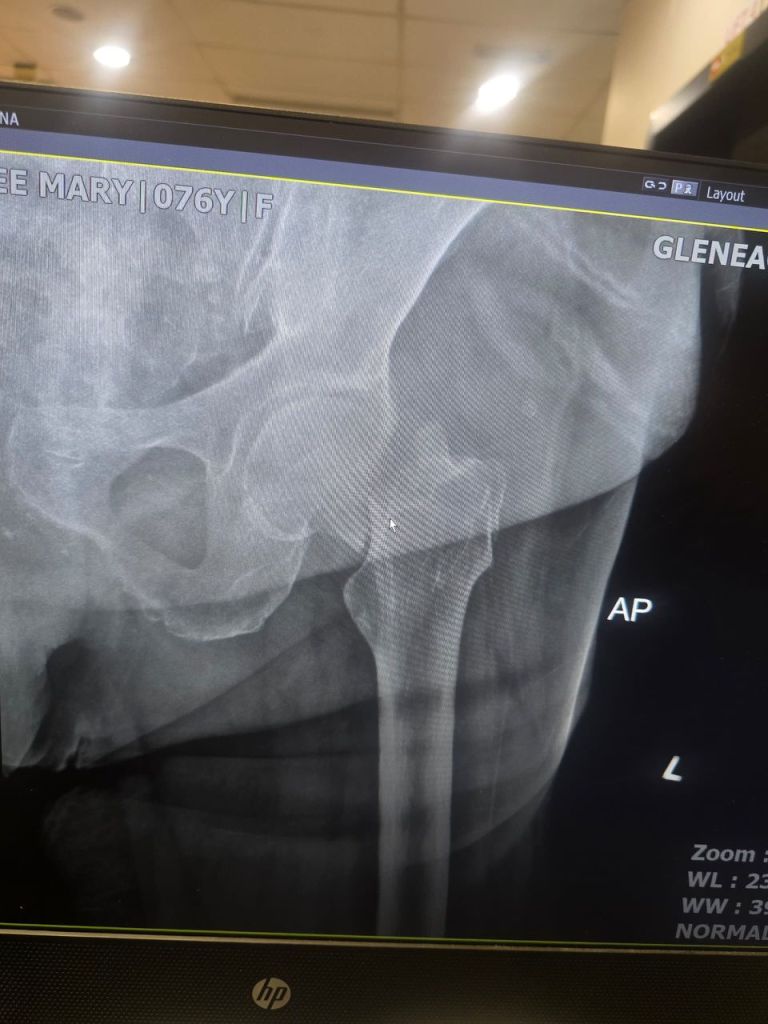

Thank God she was awake and aware, though clearly in pain. At the Emergency Department, we got her x-ray done right away and the news hit hard. A fractured neck of femur.

Mum now needs a hip replacement.

During those days in the hospital, sleep was rare. But I’m so grateful I made the decision to get the x-ray done. That one step helped us see the truth early and gave Mum the care she needed, right on time.